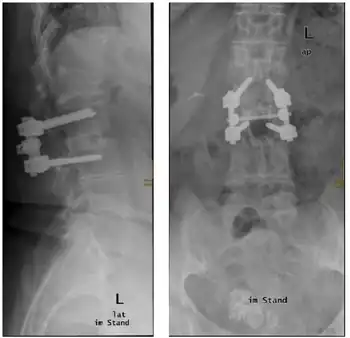

An MRI is used in the process of making a diagnosis for this condition